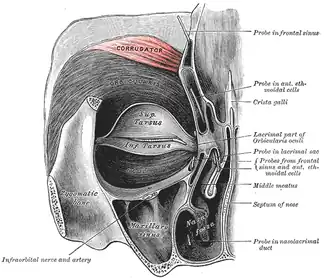

Anatomical right orbicularis oculi muscle (notice the corrugator muscle at the top) | |

Corrugator supercilii seen from the inside.

Corrugator supercilii seen from the inside. -